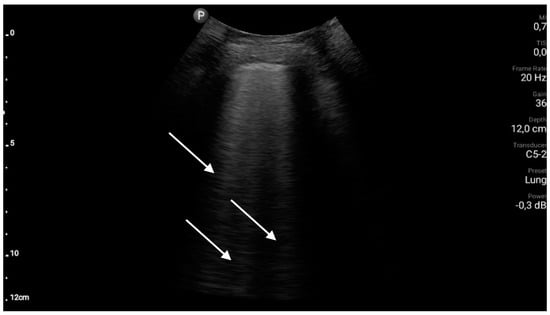

- The sonographic features of interstitial syndrome are as follows: the presence of lung sliding and ≥3 B-line artifacts in one intercostal space in a single longitudinal scan plane (in relation to the body axis). (A1)

- B-line artifacts are laser-like vertical reverberation artifacts arising from the pleural line, extending to the bottom of the screen, and moving along with the movements of the pleural line. The definition of a B-line artifact is based on the use of convex/micro-convex transducers.

Cardiogenic Pulmonary Edema and Heart Failure

- The sonographic features of cardiogenic pulmonary edema are as follows: most frequently bilateral, gravitational and symmetrical interstitial syndrome, and/or alveolar-interstitial syndrome and/or the white lung sign. (A1)

- Interstitial syndrome, alveolar-interstitial syndrome and the white lung sign define successively occurring more advanced stages of interstitial lesions in the course of cardiogenic pulmonary edema. All three of these signs require that at least three B-line artifacts be found in one intercostal space in a single longitudinal scan plane (in relation to the body axis); however, the distance between individual B-line artifacts decreases with an increasing fluid volume in the interstitial space and in the alveoli.